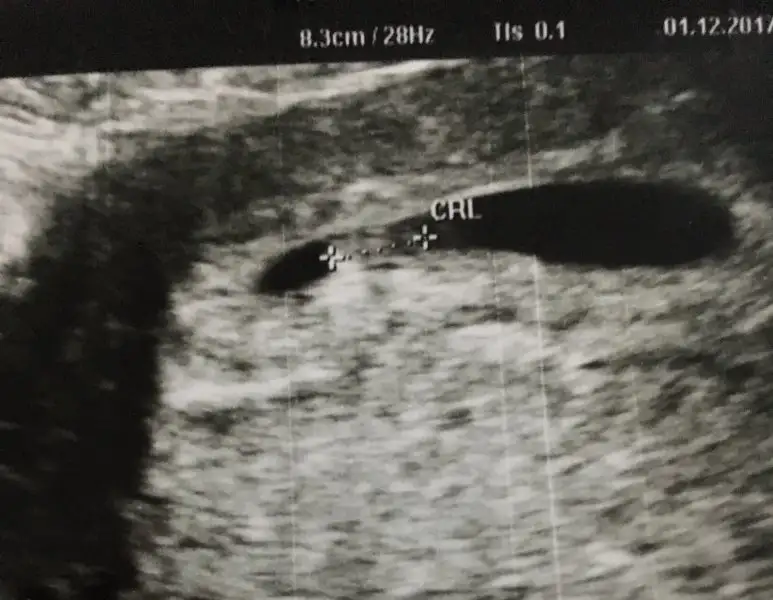

Erkek olabilir canimAnlayan arkadaşlarım benim bebisimin cinsiyet tahmini sizce ne olabilir 10. Haftamızdayız bu usg 6+6 da çekildi

Canım ramziye göre kız olabilir.Eki Görüntüle 2076071

Erkeğe benzettim canım sağlıkla gelsin ınş.Eki Görüntüle 2076088

Kesedeki konumuna göre kız gibi canın